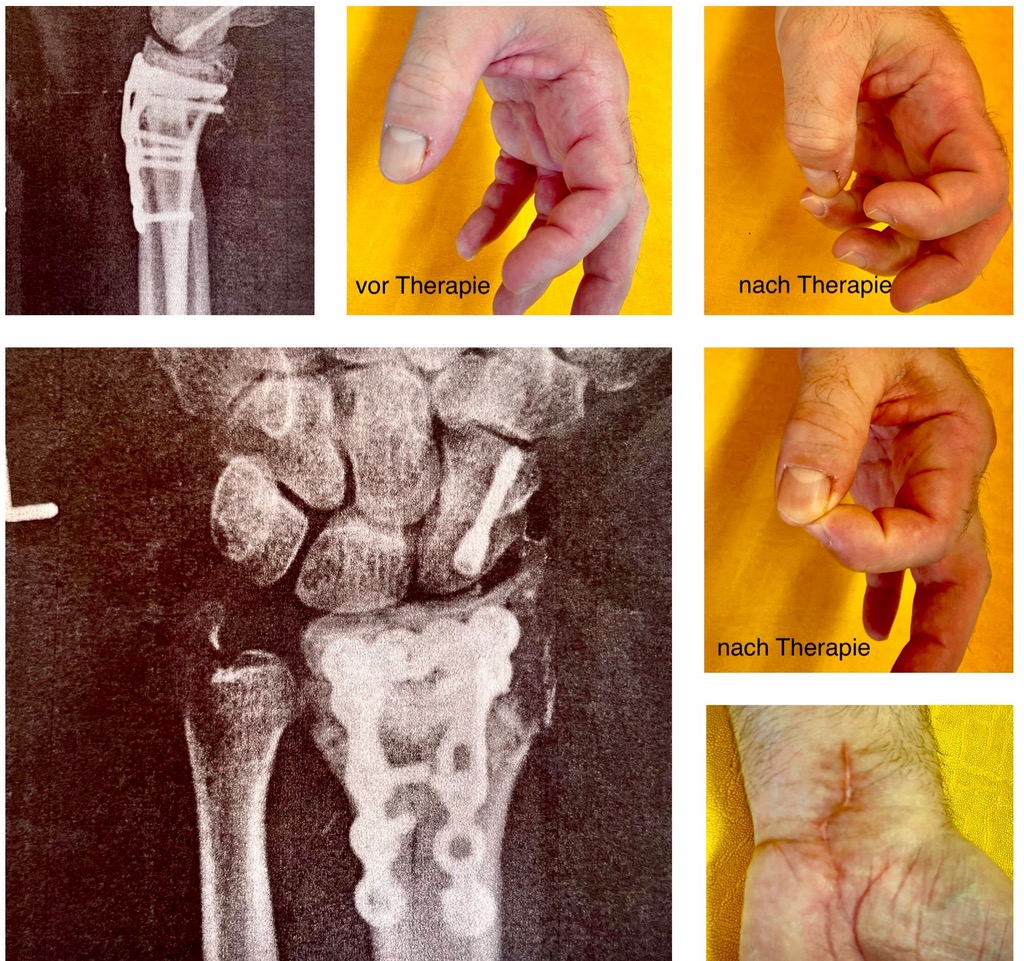

bei rheumatischen Erkrankungen, Fibromyalgie, Karpaltunnelsyndrom

insbesondere nach Handoperationen, Nerven- und Sehnenverletzungen

bei Gefühlsempfindungsstörungen insbesondere nach Operationen

Verbesserung der Gelenkbeweglichkeit

Minderung von Sensibilitätsstörungen